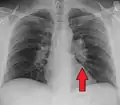

Chest radiograph changes are divided into four stages:[105]

- bihilar lymphadenopathy

- bihilar lymphadenopathy and reticulonodular infiltrates

- bilateral pulmonary infiltrates

- fibrocystic sarcoidosis typically with upward hilar retraction, cystic and bullous changes

Although people with stage 1 radiographs tend to have the acute or subacute, reversible form of the disease, those with stages 2 and 3 often have the chronic, progressive disease; these patterns do not represent consecutive "stages" of sarcoidosis. Thus, except for epidemiologic purposes, this categorization is mostly of historic interest.[28]

Hilar adenopathy especially on the person's left (AP CXR)